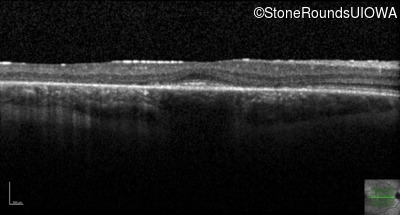

Age at visit: 30 years

This 30 year old man first noticed poor vision in dim light when he was five years old. His visual acuity began to fall in his early 20's.

Age at visit: 32 years